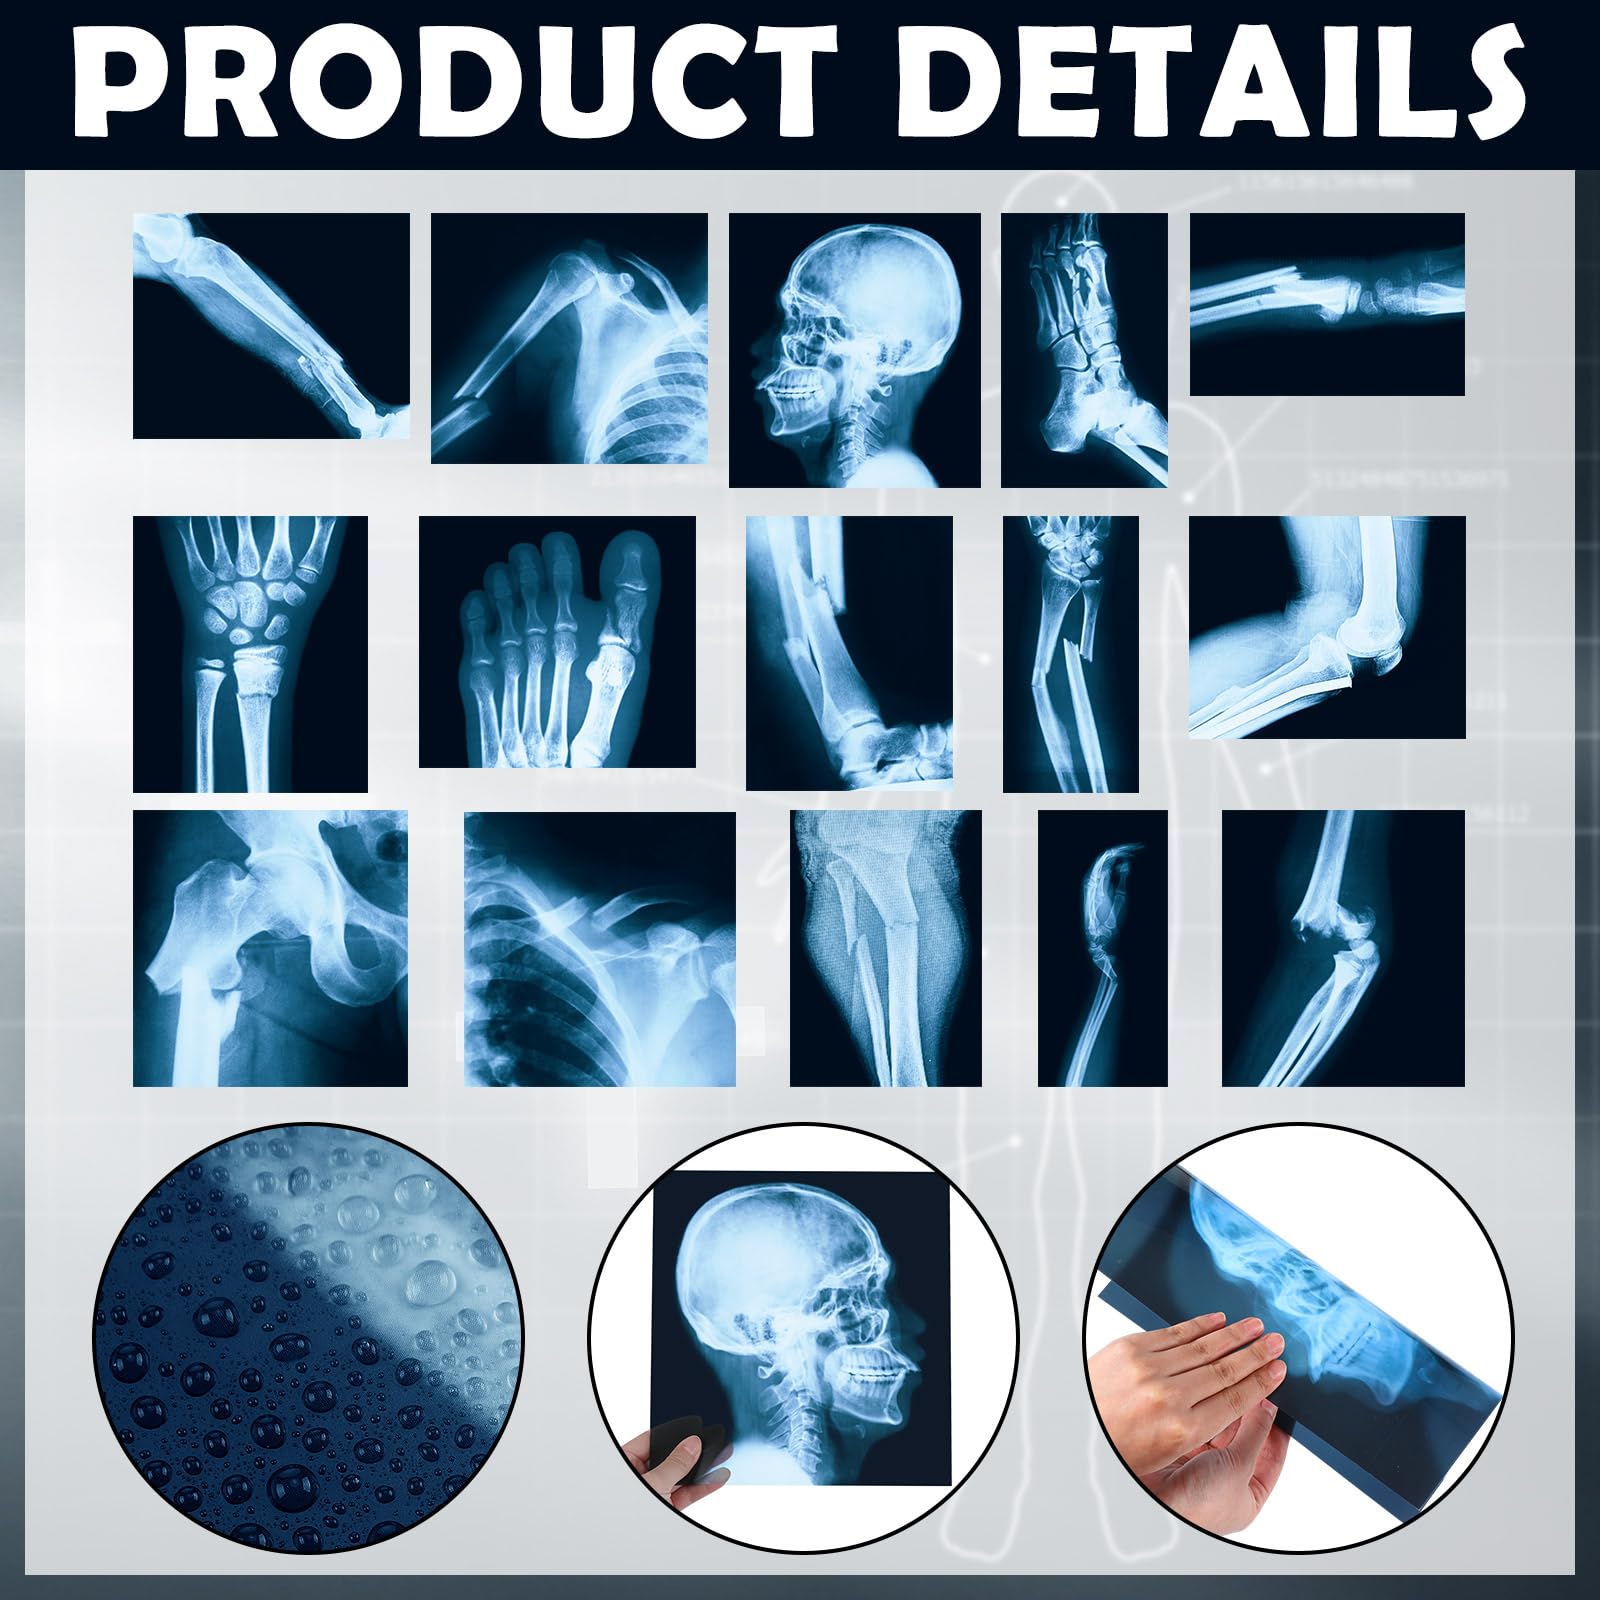

The 15 Pcs Broken Bones X Ray Set is an educational kit designed for children to explore and learn about human anatomy. Featuring 15 large, clear X-ray images of broken bones, this set is made from durable PVC plastic, ensuring safety and longevity. Perfect for classrooms or home use, it serves both educational and decorative purposes.